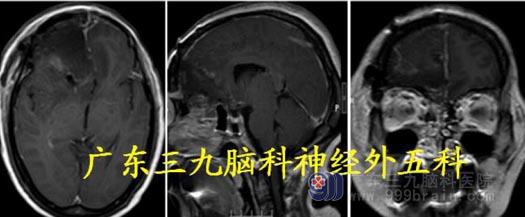

诊断:前颅底巨大占位:脑膜瘤?

头颅MR:前额部右侧示团块状长T1 稍长T2 异常信号,FLAIR 序列呈稍高信号,病灶内可见小血管影;增强后明显强化,范围约65.9mm×47.6mm×50.6mm,右侧海绵窦区血管受压增粗、瘤灶边缘可疑脑膜尾征,并局部凸入嗅束区,考虑脑膜瘤可能性大;待排HPC/SFT。

再经冠状入路行前颅底巨大脑膜瘤切除术。镜下见肿瘤起源于大脑镰及前颅底,阻断肿瘤血供后,予以钨刀切除左侧额部部分肿瘤,再予以超吸切进行瘤内减压,镜下全切肿瘤,肿瘤血供丰富,术中出血约1000ml,肿瘤前后回流静脉保护良好。

术后复查MR 显示肿瘤切除彻底,病理:孤立性纤维性肿瘤/血管周细胞瘤,G3(相当

于间变性血管周细胞瘤),WHO III 级。